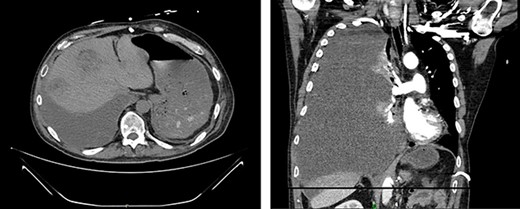

First appearance of multiple liver lesions suspicious for metastasis in transverse (left) and coronal (right) planes on CT; reduction of retroperitoneal effusion can also be seen.

Serial CT scans at 10 and 12 weeks post-resection revealed reduction of the retroperitoneal abscess and appearance of liver lesions concerning for metastasis (Fig. 4). The patient eventually completed his radiation course with no additional problems.